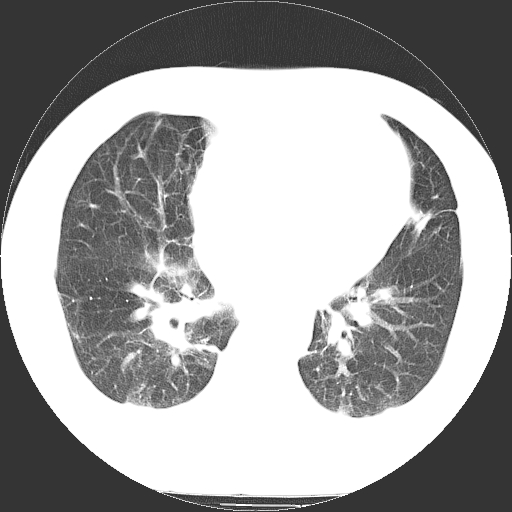

标题: CT21804:男,65岁,咳嗽、咳痰、发热5天。 [打印本页]

男,65岁,咳嗽、咳痰、发热5天。

支持慢性支气管炎伴感染,双侧少量胸腔积液.

两肺间质纤维化,支扩合并感染,双侧胸腔积液

慢性支气管炎并感染,支扩,双侧少量胸腔积液.